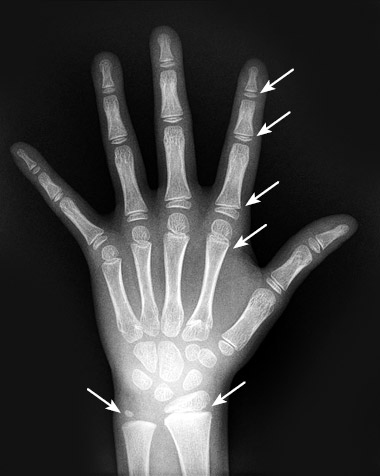

На разных костях это происходит в разное время, однако последовательность всегда предсказуема, так что ортопеды и рентгенологи, взглянув на рентгеновский снимок кисти руки, могут определить возраст и степень зрелости скелета по активности эпифизарных пластинок. Для антропологов наличие или отсутствие ростовых пластинок на определенных костях считается признаком возраста человека на момент его смерти.

Иллюстрация к книге — Кости: внутри и снаружи [i_013.jpg]

Эпифизарные пластинки (показаны стрелками) имеются на концах всех трубчатых костей руки этого семилетнего ребенка и обеспечивают их рост. Когда в подростковом возрасте рост костей в длину завершается, эпифизарные пластинки сливаются с телом кости

Benjamin Plotkin, MD